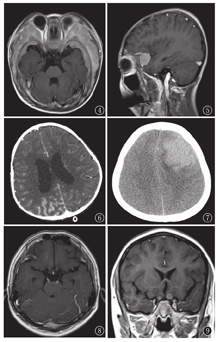

共23例,包括硬脑膜、软脑膜、脑实质、颅骨和颅神经的浸润,部分病例兼有2种或2种以上浸润形式。23例中硬膜伴和/或伴颅骨浸润18例,表现为硬膜和/或颅骨梭形或结节、肿块样增厚,颅骨以颅底骨受累显著,可跨颅板(图4)。病灶在CT上呈较高密度,T1WI低信号,T2WI中等信号,增强检查明显强化(图5);软脑膜浸润6例,表现为软脑膜广泛或局限性增厚、强化(图6);脑实质浸润2例,CT表现为高密度肿块(图7),MRI T1WI低信号、T2WI中等信号肿块伴周围脑实质水肿;颅神经浸润3例,MRI表现为2例动眼神经(1例单侧,1例双侧,图8)、1例双侧视神经增粗强化(图9)。

颅脑浸润包括硬脑膜浸润、软脑膜浸润、脑实质浸润、颅骨浸润及其混合型,均可呈弥散性或局限性[9]。脑膜浸润,一般认为是白血病细胞经脑膜血管向蛛网膜下腔播散的结果,MRI增强后FLAIR序列可清晰显示脑膜增厚、强化,因此怀疑脑膜浸润时应行此序列检查。粒细胞肉瘤见于粒细胞白血病[10],于起病或复发时出现,儿童较成人更易发生,可发生于全身多部位,尤其颅脑、眼眶、鼻窦,在颅脑可弥散性或局限性侵犯硬脑膜、软脑膜、脑实质、颅骨。CT表现为高密度,单凭CT值与脑内血肿难以鉴别,需结合凝血指标、皮肤有无出血点、SWI等。MRI检查T1WI呈低信号,T2WI呈中等信号,增强检查明显强化。

颅神经麻痹是白血病颅内浸润的典型表现之一,最常受累的是单侧面神经[11]。颅神经浸润与否对白血病初诊时CNS状态分级有重要意义,CNS 3级的诊断标准为CSF中存在白血病细胞(计数≥5×106)或存在颅神经麻痹或影像学检查显示头颅肿块[12]。本组3例临床症状有视物重影、模糊,MRI检查发现2例动眼神经、1例视神经增粗强化,提示颅神经浸润,因此支持临床将其归为CNS状态3级。